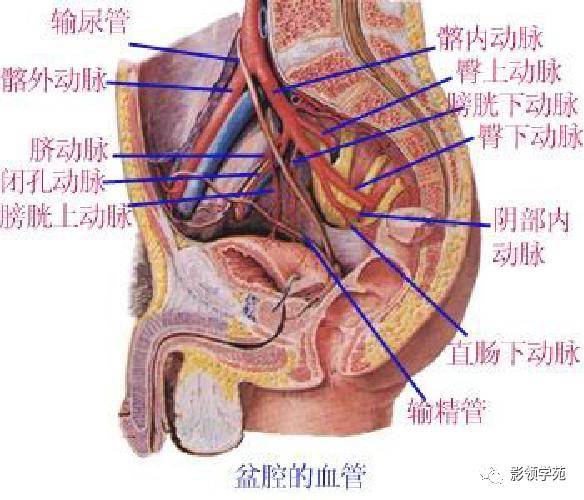

腹部动静脉

腹部动静脉